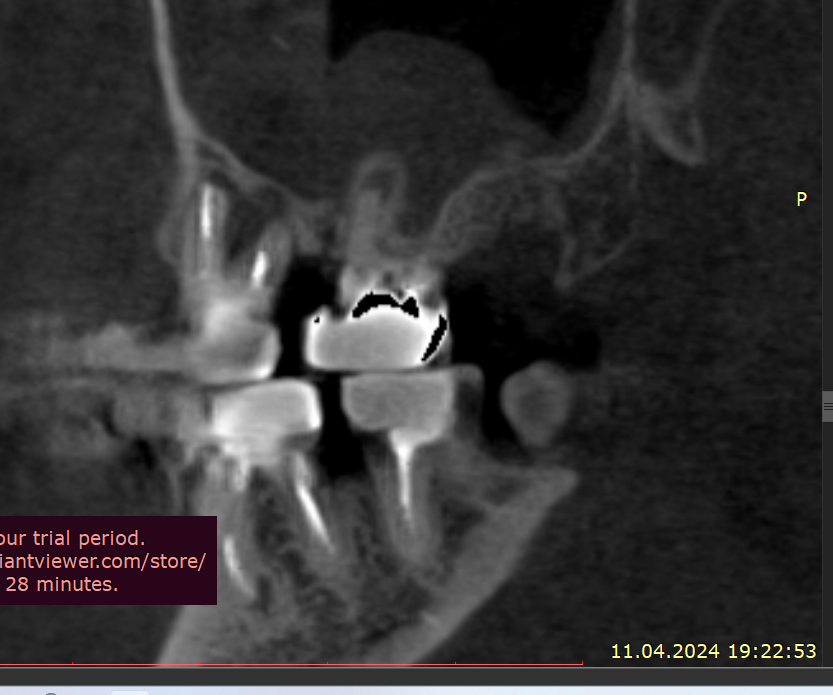

Добрый вечер Подскажите пожалуйста, вчера ел арахис, это очень редко бывает и мне такое противопоказано, и слышу один твёрдый попался немного, в момент когда накусил немного в области 4–5 зуба вверху справа, почувствовал боль, которая по сейчас сохраняется, боль чувствую именно в периодонте (к сожалению кто меня помнит с моей историей длительной я уже знаю как отличать боль по чувствительности, ту или иную), делал КЛКТ 3 недели, просто планово по поводу других зубов, посмотреть что и далее сохраняется положительная динамика после больших перенесённых периодонтитов, в вот посмотрел заодно на вот эти (открыл дайком) где вчера накусил, там нет и не было деструкции кости, зубы давно мертвые и нужно менять реставрации, зубы эти при надавливании пальцем не болят, жевать тоже не усиливается, просто ноющая периодонтальная боль извините за сленг, острой боли прям в момент накусывания арахиса тоже не было

Так же посоветуйте пожалуйста, как лучше поступить в случае 24-26, почти 2 года назад был большой периодонтит, киста пазухи. карман между 26\27, предварительно это удалось вылечить, уже 9 месяцев ничего там не болит, все спокойно, по кт медленно но есть положительная динамика, хотя все говорили удалять и только, возможно прям долгие годы эти зубы не простоят, но я хотел снять адегизивный, коронка, которая закрывает 25 отсутствующий, она крепится бабочкой между 26 и 24, и по хорошему коронки на 24,25,26 мост сделать, некоторые говорят имплант между 25, а 24 и 26 сделать просто реставрацию, я уже запутался, как лучше будет поступить ? Имплантат пока не хотел лишь по причине перенесенного в почти полтора года лонг ковида, это ужасный диагноз, в том виде в котором был у меня по крайней мере, и я хотел бы пока избежать более инвазивных процедур, хотя бы ближайшие пару лет, далее видно будет, но функционально и эстетически нужно наводить порядок, чем я и начал заниматься

Рентген сегодня сделал, трещины нет, но я слышал не на рентгене не на клкт часто трещины не видны, и лишь только под микроскопом